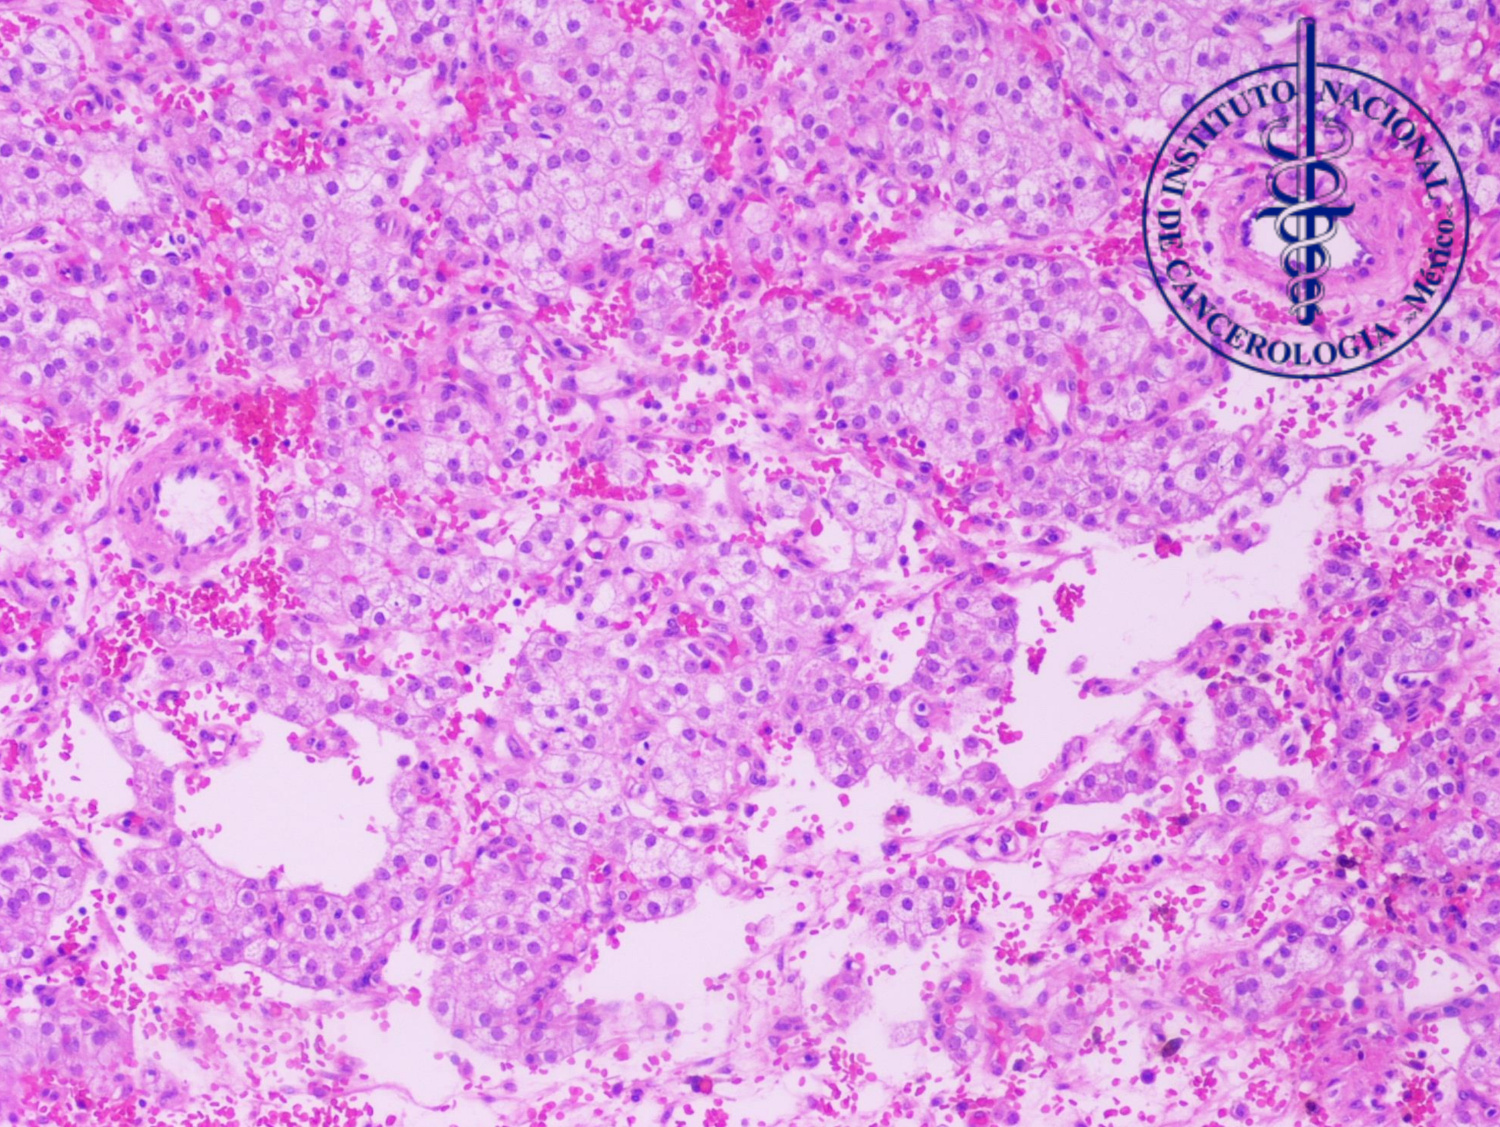

1.¿Con base en el cuadro clínico y los hallazgos histopatológicos, cual sería su diagnóstico?

A. Tumor de células esteroideas

B. Tumor de células de Sertoli

C. Metástasis de carcinoma renal de células claras

D. Carcinoma de células claras del ovario